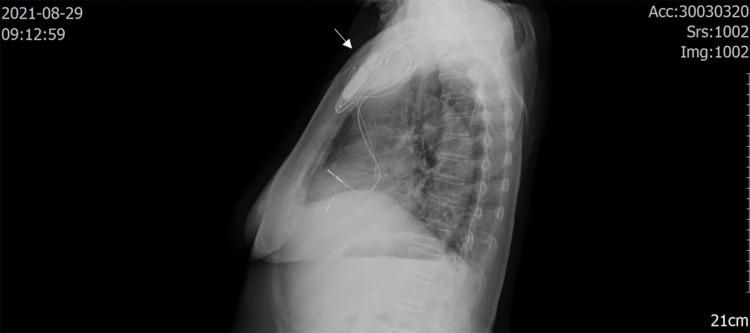

is a recognized pathogen in patients with immunodeficiency and a normal immune response, which can cause bacteremia, endocarditis, peritonitis and pulmonary infection. We report a case of wound infection after pacemaker implantation caused by . Matrix-assisted laser desorption time-of-flight mass spectrometry (MALDI-TOF MS) was routinely used to identify the pathogen, and the results showed that the pathogen could not be accurately identified in the MALDI-TOF database at present. The 16S rRNA gene of the pathogen was further sequenced, and the result was . To the best of our knowledge, this is the first reported case of human infection caused by .

是免疫缺陷患者和免疫反应正常患者中一种公认的病原体,可引起菌血症、心内膜炎、腹膜炎和肺部感染。我们报告一例起搏器植入术后伤口感染病例,由……引起。常规使用基质辅助激光解吸飞行时间质谱(MALDI-TOF MS)鉴定病原体,结果表明目前在MALDI-TOF数据库中无法准确鉴定该病原体。对该病原体的16S rRNA基因进行进一步测序,结果为……。据我们所知,这是首次报道的由……引起的人类感染病例。